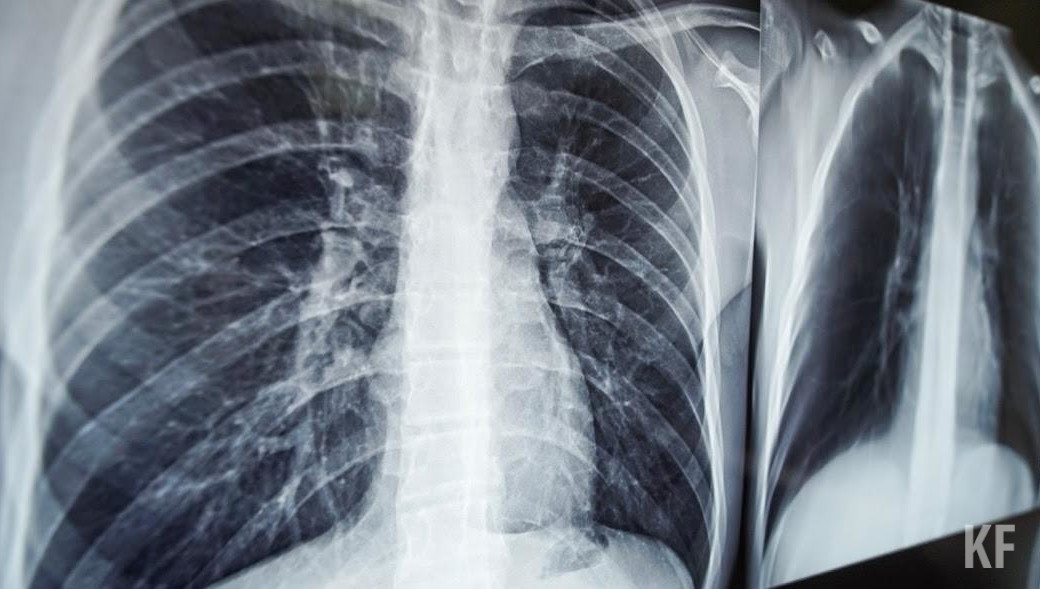

Индийский штамм коронавируса опаснее других видов из-за быстрого поражения легких. Об этом в интервью «Ленте.ру» рассказала профессор Школы системной биологии Университета Джорджа Мейсона (США) Анча Баранова.

По словам специалиста, функция легких при нем падает гораздо быстрее.

— Пациент поступает в больницу с КТ-2 [вторая степень поражения, выявленная с помощью компьютерной томографии], завтра у него уже КТ-3, а послезавтра он в реанимации, — пояснила Баранова.

При заболевании коронавирусом клетки эпителия прекращают производить смесь веществ, покрывающую легкие изнутри. А затем клетки превращаются в фибробласты и «уже ничего хорошего производить не смогут, кроме провоспалительных цитокинов и других пакостей», рассказала эксперт.